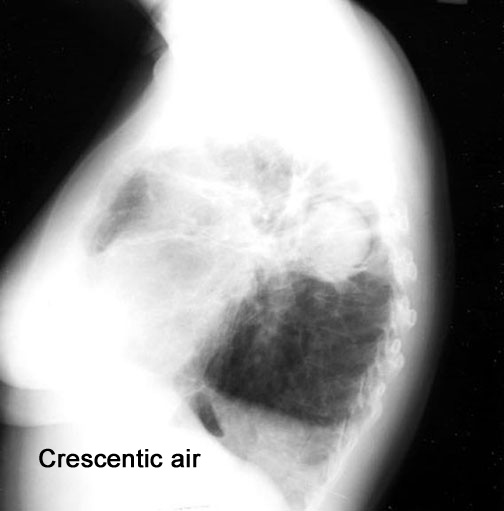

Case 23

Lateral

Upright

Lateral upright

Supine

Lateral decubitus

What are the common cavities where fungous ball forms?